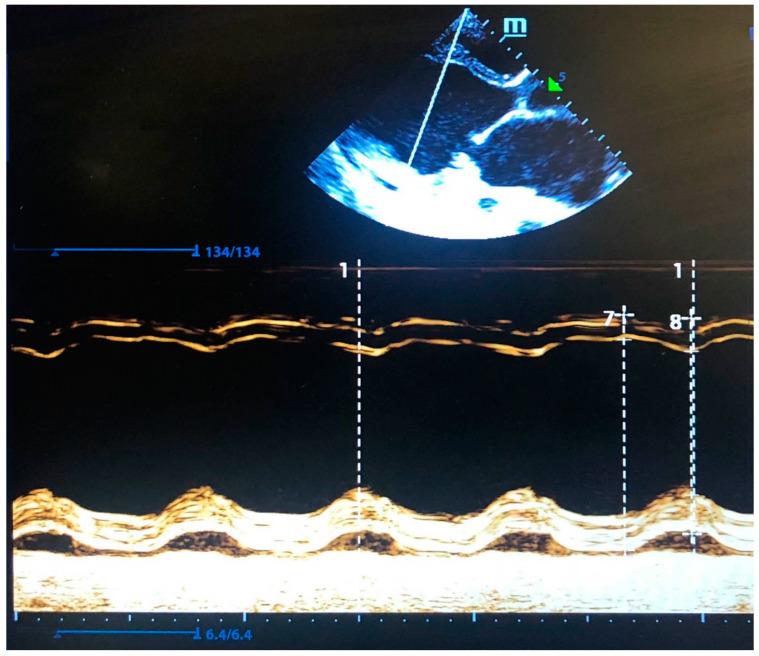

Intellectual disability with developmental delay is the most common developmental disorder. However, this diagnosis is rarely associated with congenital cardiomyopathy. In the current report, we present the case of a patient suffering from dilated cardiomyopathy and developmental delay.

Trio sequencing revealed a de novo missense variant in the gene (p.Arg275His), that is, according to the OMIM database and available literature, not currently associated with any specific inborn disease. The expression of Ca/calmodulin-dependent protein kinase II delta (CaMKIIδ) protein is known to be increased in the heart tissues from patients with dilated cardiomyopathy. The functional effect of the CaMKIIδ Arg275His mutant was recently reported; however, no specific mechanism of its pathogenicity was proposed. A structural analysis and comparison of available three-dimensional structures of CaMKIIδ confirmed the probable pathogenicity of the observed missense variant.

We suggest that the CaMKIIδ Arg275His variant is highly likely the cause of dilated cardiomyopathy and neurodevelopmental disorders.